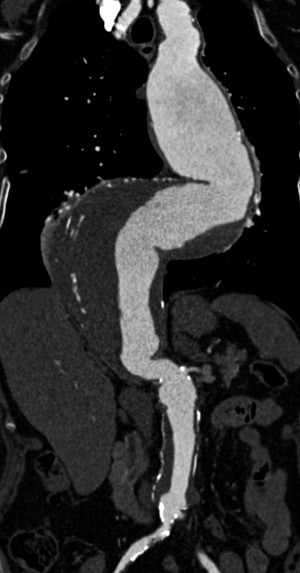

Den viktigste bildediagnostiske metoden ved torakoabdominalt aortaaneurisme er CT-undersøkelse med kontrast (fig 2). Både torakal- og abdominalaorta samt bekkenkar bør fremstilles. Ved alvorlig nyresvikt kan MR-undersøkelse uten kontrast være en alternativ bildediagnostisk metode.